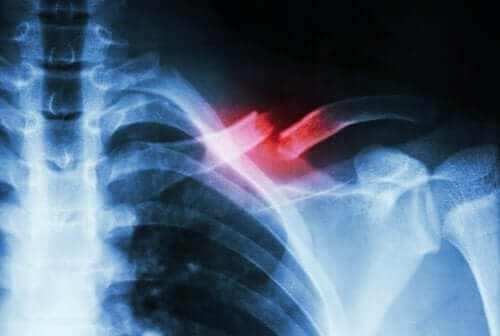

En stressfraktur forekommer, når der er et lille brud på en knogle, der har oprindelse i noget andet end et kraftigt slag. Typisk er det enten udløst af gentagende bevægelser eller af en hurtig stigning i mængden eller intensiteten af en aktivitet.

Disse typer brud er ikke nemme at diagnosticere. De kræver således en medicinsk specialist og komplementære tests for at skelne det fra andre tilstande. Dette skyldes, at bruddet normalt ikke opdages på et røntgenbillede.

Når der ikke er nogen kontinuitet i knoglevævet, skyldes det, at der er et brud. De fleste af disse skader opstår på grund af slag eller traumer. I tilfælde af en stressfraktur er årsagen til problemet ofte bare svaghed eller træthed.

En stressfraktur er en slags spalte eller en revne i knoglen. Det sker på grund af gentagende mikrotrauma eller overbelastning, som vi nævnte ovenfor. Derudover kan de udgøre svær smerte, når visse fysiske aktiviteter udføres. Derefter forsvinder de ofte, når aktiviteterne slutter.